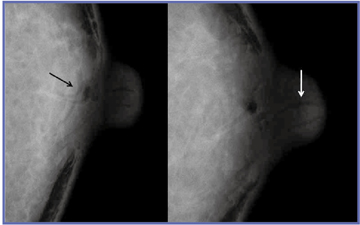

●触知情報

特に異常が認められない検診マンモグラムでも,技師からポジショニング時に腫瘤を触れたとの情報があれば,注意深く観察できる。図2はそのような症例で,MLO像(a)だけでは中心部が低濃度であるため腫瘤として取り上げられないと思われるが,CC像(b)では,技師がしこりと指摘した部位に腫瘤が認められ,精密検査となった。超音波による精密検査では,しこりの部分に腫瘤が認められ,悪性も否定できなかった。針生検で線維腺腫との診断で,経過観察となった。